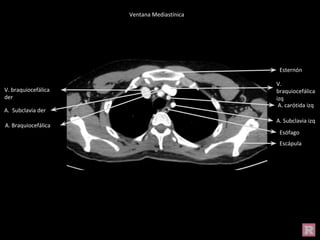

Ventana Mediastínica

Esternón

Escápula

V.

braquiocefálica

izq

V. braquiocefálica

der

A. carótida izq

A. Subclavia izq

A. Braquiocefálica

A. Subclavia der

Lóbulo superior

Esófago